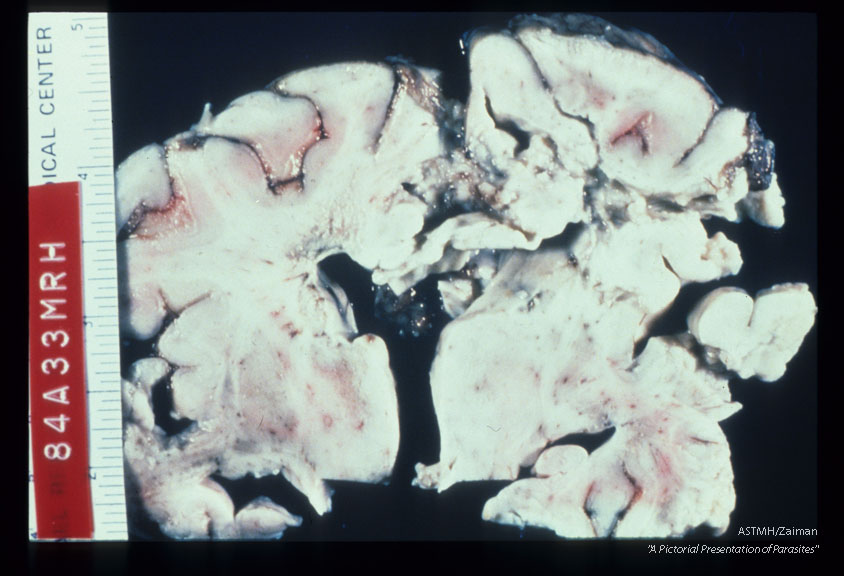

A one and one half year old boy died after a 3 week bout of CNS disease. Brain shows peri-ventricular necrosis and softening.

Description: A one and one half year old boy died after a 3 week bout of CNS disease. Brain shows peri-ventricular necrosis and softening.